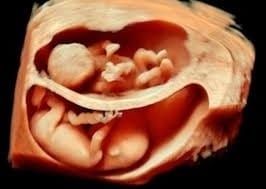

- Ecografia ostetrico-ginecologica

- Ecografia in gravidanza con valutazioni morfologiche

Ecografia Ginecologica/Ostetrica. Utilizziamo sonde dedicate (fino a 13 mhz) per visualizzazioni superficiali e profonde, inclusi studi avanzati 3D e 4D. L'ecografia mammaria, spesso integrata con la visita senologica e la mammografia (pacchetto senologico), è un pilastro della nostra attività di screening. I nostri specialisti garantiscono l'affidabilità della